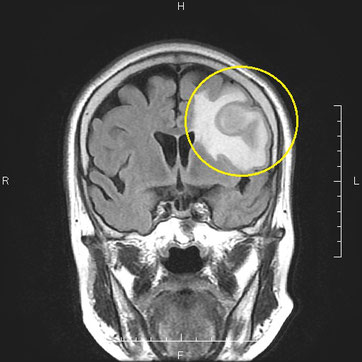

専用出品!mri〜様 □当クリニックの放射線科 - あぜみち脳神経クリニックの詳細情報

□当クリニックの放射線科 - あぜみち脳神経クリニック。4535-670-61683 - Philips - MRI - 8 Channel Sense Knee Coil。放射線科 | 浅草寺病院 | Sensoji Hospital。Signa HDxtのNewアプリケーションと標準化の取り組み-技術解説。緑と黒のドレスを着た女性のポートレート